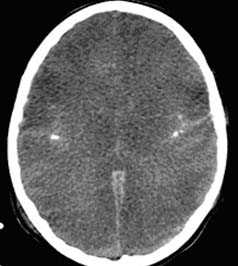

По причине мягкой семиотики сотрясения головного мозга и возможности возникновения подобной картины в результате одной из многих дотравматических патологий, особое значение в диагностике придается динамике клинических симптомов. Обоснованием диагноза «сотрясение мозга» является исчезновение таких симптомов через 3-6 суток после получения черепно-мозговой травмы. При сотрясении мозга отсутствуют переломы костей черепа. Состав ликвора и его давление сохраняются в норме. На КТ головного мозга не определяются внутричерепные пространства.

Всех пострадавших с черепно-мозговой травмой в обязательном порядке транспортируют в стационар, где после подтверждения диагноза устанавливают им постельным режим на срок, который зависит от клинических особенностей течения заболевания. Отсутствие признаков очаговых поражений головного мозга на КТ и МРТ головного мозга, а также состояние пациента, позволяющее воздержаться от активного медикаментозного лечения, позволяют решить вопрос в пользу выписки пациента на амбулаторное лечение.